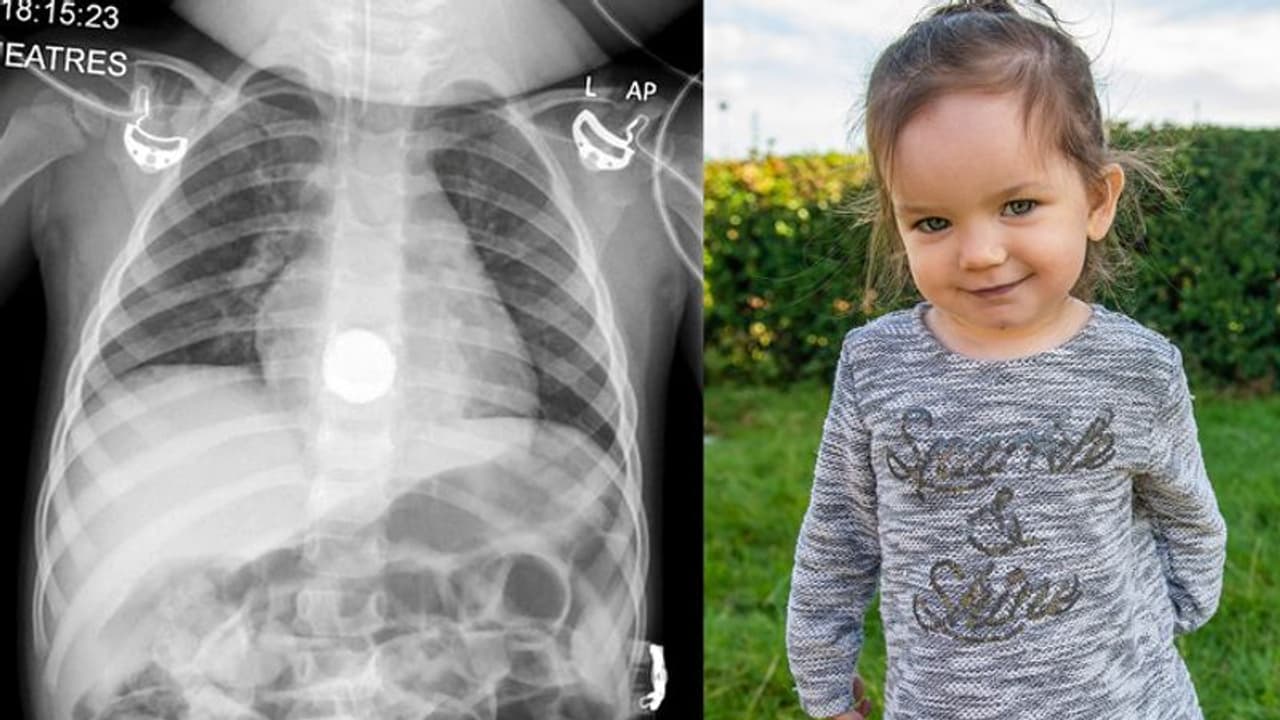

എക്സ് റേയിൽ ബാറ്ററി നെഞ്ചിന് താഴേ എത്തിയിട്ടുള്ളതായി കണ്ടെത്താനായി. ശസ്ത്രക്രിയ നടത്തുക എന്നുള്ളതായിരുന്നു ആകെയുള്ള പോംവഴിയെന്ന് സൗത്ത് യോർക്ക്ഷോറിലെ ഷെഫീൽഡ് ചിൽഡ്രൻസ് ഹോസ്പിറ്റലിലെ ഡോക്ടർമാർ പറഞ്ഞു.

ചെറിയൊരു വയറുവേദനയായിട്ടാണ് മകൾ എൽസിയെ ആശുപത്രിയിൽ പ്രവേശിപ്പിച്ചത്. ഇടവിട്ട് വയറ് വേദന വരാറുണ്ടെന്ന് കുഞ്ഞ് പറയാറുണ്ടായിരുന്നു. ഡോക്ടറെ കണ്ടപ്പോൾ വിദഗ്ധപരിശോധന നടത്തണമെന്ന് അവർ പറഞ്ഞു. അങ്ങനെയാണ് ഉള്ളില് മാരകമായ ലിഥിയം ബാറ്ററി കുടുങ്ങി കിടക്കുന്നുണ്ടെന്ന് കണ്ടെത്തിയത്. കുഞ്ഞിന്റെ ജീവൻ പോലും നഷ്ടമായേക്കാമെന്ന് ഡോക്ടർമാർ പറഞ്ഞു.

കുഞ്ഞിന്റെ തൊണ്ടയ്ക്കും അന്നനാളത്തിനും ഇടയിലായിട്ടായിരുന്നു ബാറ്ററി കുടുങ്ങി കിടന്നിരുന്നത്. കുഞ്ഞ് ബാറ്ററി വിഴുങ്ങിയിട്ട് 24 മണിക്കൂറോളം കഴിഞ്ഞിരുന്നു. അപ്പോഴേക്കും ബാറ്ററി എല്സിയുടെ തൊണ്ടയിലിരുന്നു പുകഞ്ഞ് ഒരു മുറിവുണ്ടാക്കിയിരുന്നു.